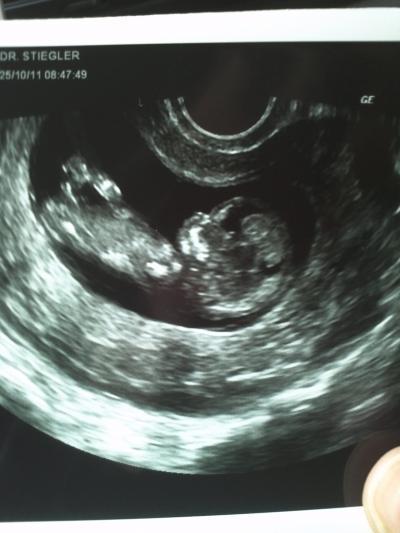

Seit ich schwanger bin, bin ich dauernd erkältet und mittlerweile hatte ich schon etwas Sorge das es dem Baby eventuell nicht gut gehen könnte dadurch und bin heute zu meinem Arzt. Der hat mir natürlich gesagt, das macht dem Baby nichts und hat auch mir zu liebe geschallt. Und siehe da unseren kleinen Schatz geht es total prima!! Hat sich schon richtig bewegt und es war sooooo schön Lg Susi

Bild zu War heute ausserplanmässig beim Frauenarzt... - Forum für Mai - Mamis

Hallo Susi, oh man, was ein tolles Bild!!! Wundersch;n!!!! Lg Susanne

Oh,was für ein wunderschönes Bild!